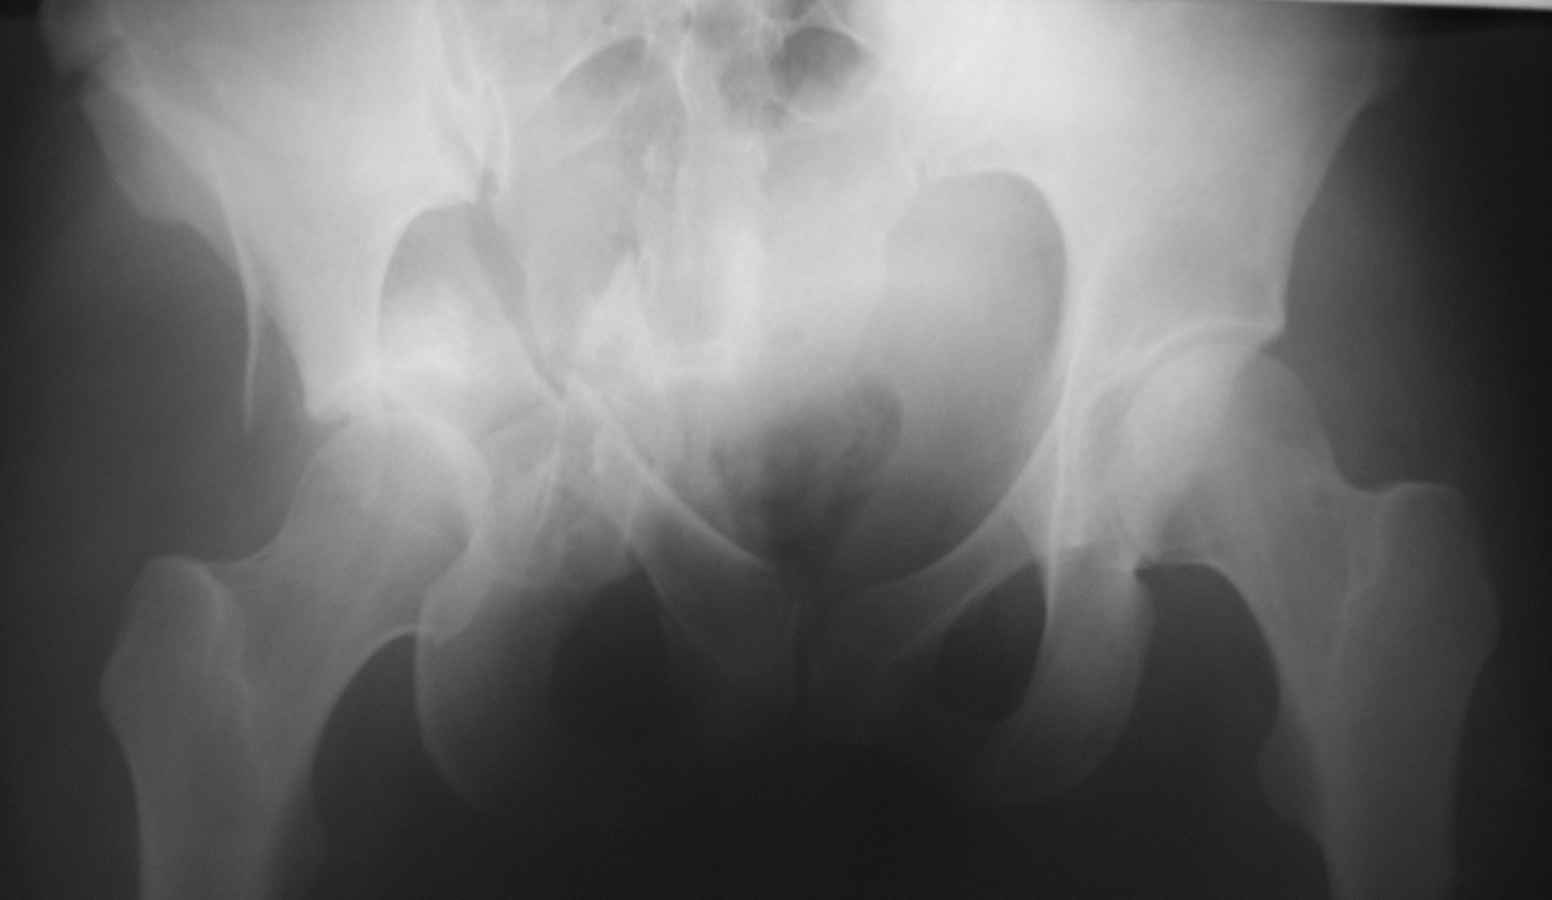

Это не "цетральный вывих", а двухколонный перелом вертлужной впадины. Лучше прооперировать, я бы выбрал подвздошно бедренный доступ, хотя можно и из бокового чрезвертельного.

Оскольчатый двухколонный перелом, лучше отправить пациента туда, где занимаются лечением "центральных вывихов" бедра.

Тут перелом достаточно сложный и говорить о характере перелома можно после дополнительных методов исследования. Нужны проекции Judet для оценки передней и задней колонн (перелома передней и задней колонн видны и на этом снимке, но характер их перелома и смещение лучше видны в специальных порекциях). Нужно КТ исследование.

Большое спасибо за содержательные советы. Вот снимок при поступлении.